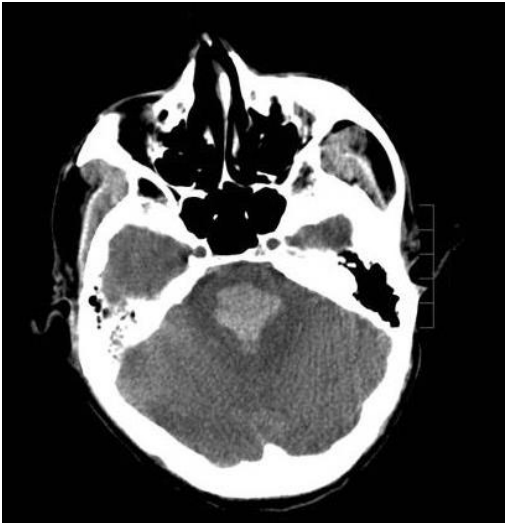

诊断:脑干出血